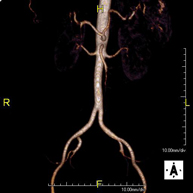

- Aortic-iliac MRI angiography

A non-invasive diagnostic test that involves studying the abdominal aorta and iliac arteries, obtaining high-definition anatomical images using an electromagnetic field and radio waves (with transmitter and receiver). The use of paramagnetic contrast (gadolinium) is essential. However, it is a radiation-free procedure. The quality of the images allows for 2D and 3D reconstructions. This test is particularly recommended as a pre-surgical study (vascular map) prior to percutaneous or surgical interventions on the abdominal aorta and iliac arteries, as a complementary study in patients with lower limb ischaemia, etc.